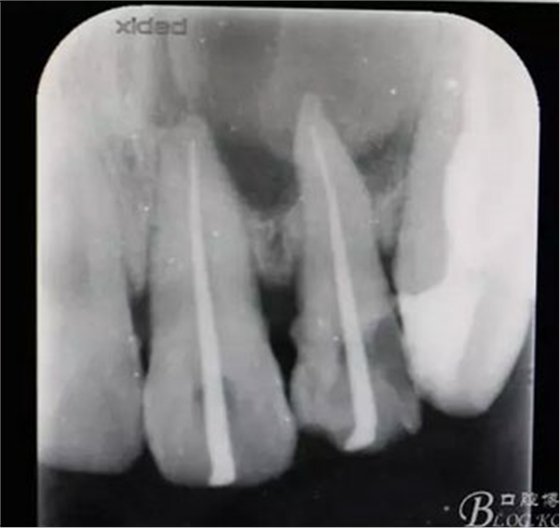

圖2.根管治療術(shù)中試尖影像

圖3.根管治療完成后的影像檢查: